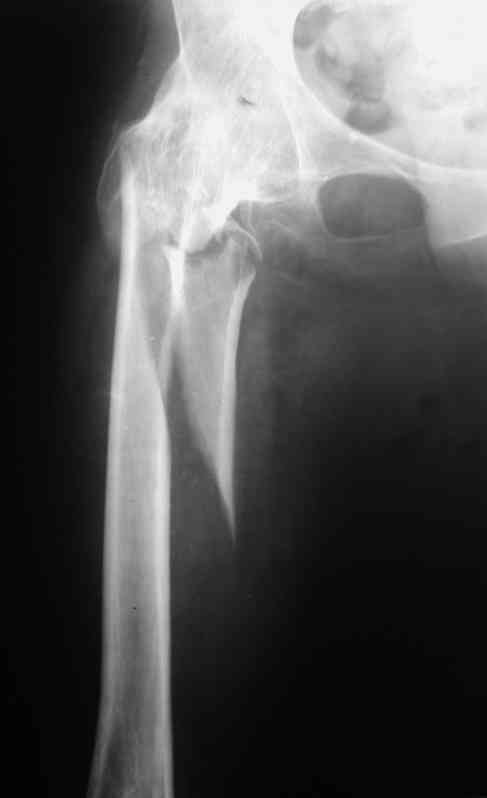

Рентгенограммы до и после. Больной профессор на кафедре сопромата и после детального изучения

особенностей имплантата, собственных рентгенограмм дал добро на операцию. Ваш вариант лечения вполне симпатичен.

С уважением А.Семенистый.